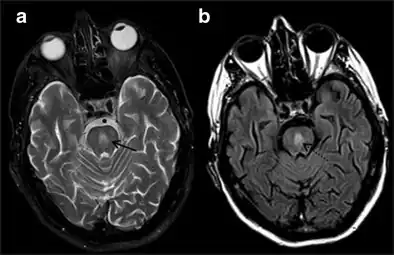

It can be diagnosed clinically in the appropriate context, but may be difficult to confirm radiologically using conventional imaging techniques. Changes are more prominent on MRI than on CT, but often take days or weeks after acute symptom onset to develop. Imaging by MRI typically demonstrates areas of hyperintensity on T2-weighted images.[27]